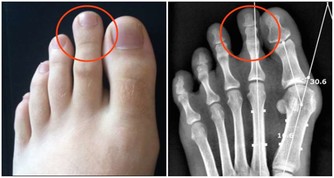

6、通過舌苔顏色可以判斷是否脾虛,健康的舌頭呈現粉紅色,表面十分潤澤。舌頭的表面有一層舌苔,健康的人舌苔十分乾淨,如果舌頭邊緣出現明顯的齒痕,說明脾臟功能出現異常。如果舌苔粗糙並且厚,還伴有發黃發膩症狀,說明體內有濕熱症狀,脾臟功能受損。